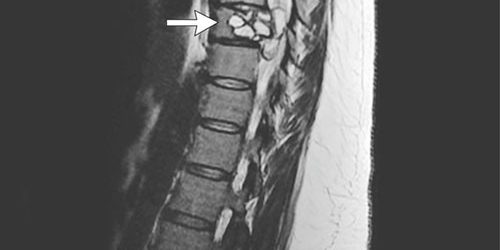

Анализы крови указывали на наличие какой-то инфекции. Но точную проблему не удавалось установить, пока магнитно-резонансная томография спины не показала поражение в IXгрудном позвонке.

При помощи хирургического вмешательства участок поражения был удален, дефект позвонка заменили протезом. Оказалось, что проблему вызвала личиночная форма собачьего цепня, которую также называют эхинококком (Echinococcusgranulosus).